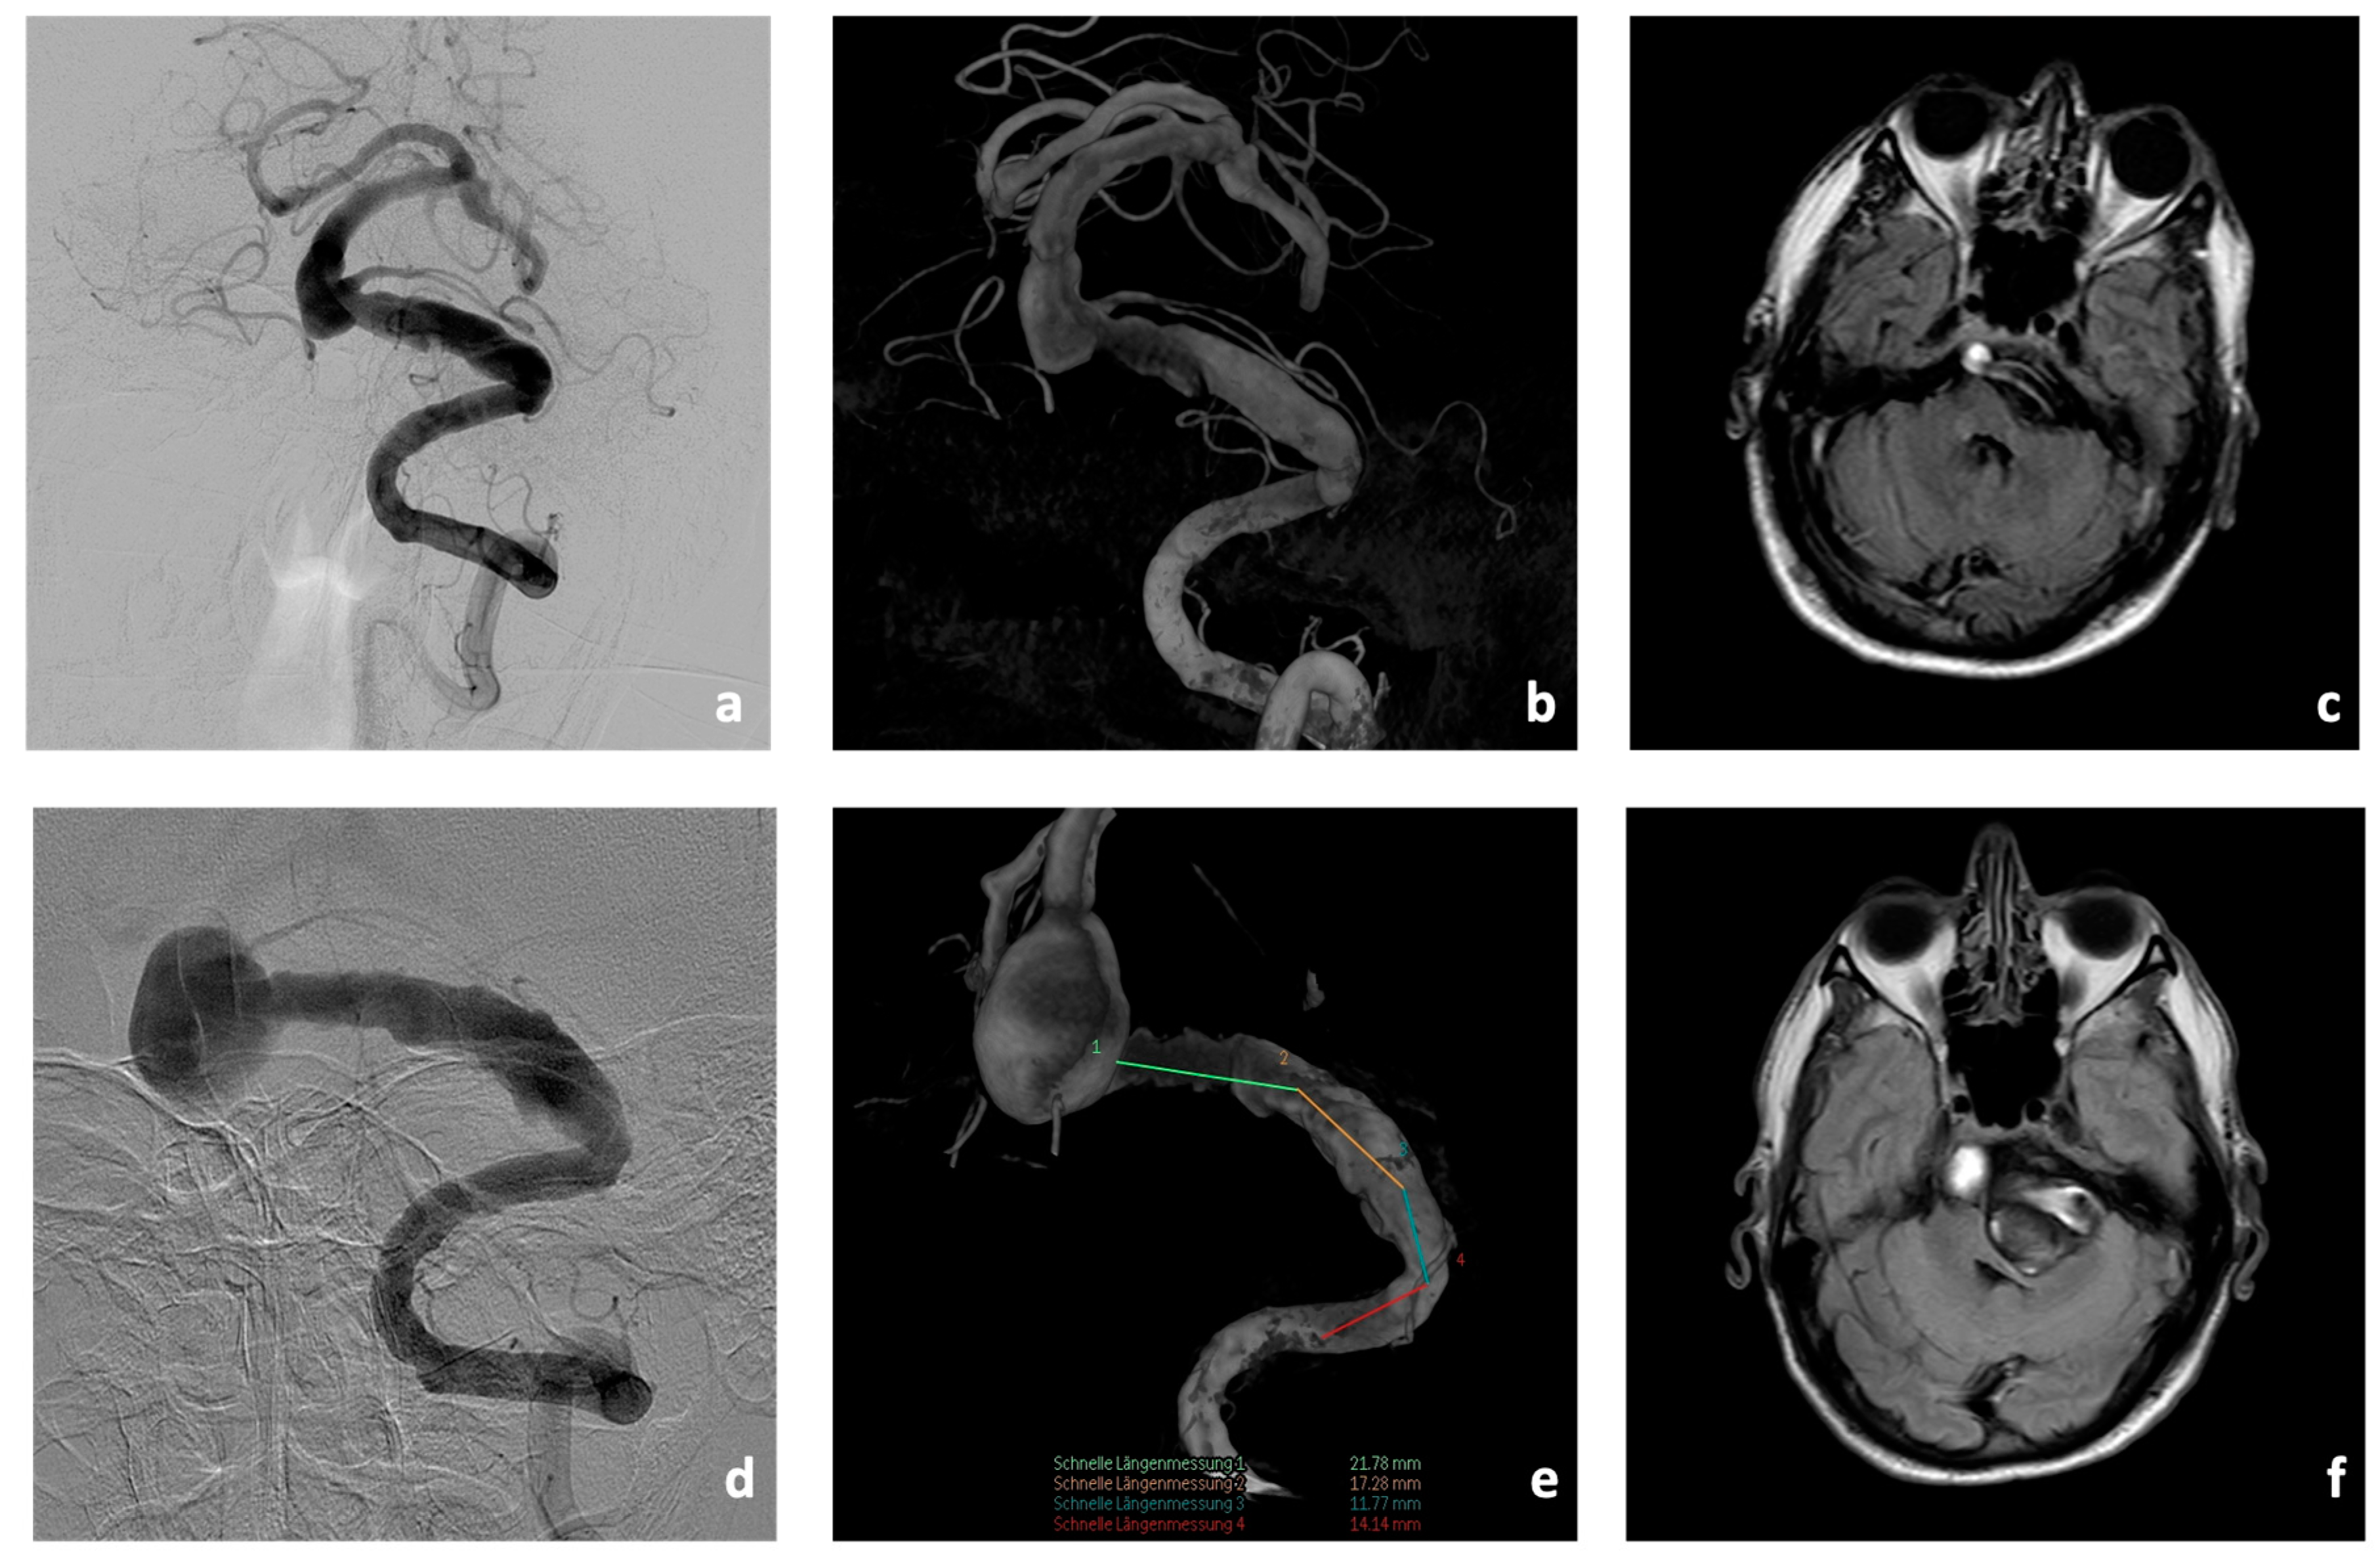

Initial cerebral imaging in 2018 with magnetic resonance imaging (MRI), computed tomography (CT), CT-angiography (CT-A), CT-perfusion (CT-P), and digital subtraction angiography (DSA) showed an aneurysm of the BA (10 × 11 mm) with concomitant fusiform caliber irregularities of the V4 segments of the left VA (35 mm in length, Figure 3). In addition, there was a hypoplastic right VA.

CTA showed a significant increase in the size of the fusiform aneurysm with a maximum BA diameter of 15 × 22 mm. In addition, at this time, there was already manifest compression and displacement of the brain stem to the right due to the fusiform aneurysm of the V4 segment of the left VA (8 × 50 mm, Figure 3).

Figure 3. Imaging findings of Patient #1 at initial presentation (ac) and four years later (df). Massive progression of the fusiform aneurysm of the V4-segment and the BA in the DSA (d,e) and in the thrombosed part (f) with increasing significant brain stem compression.